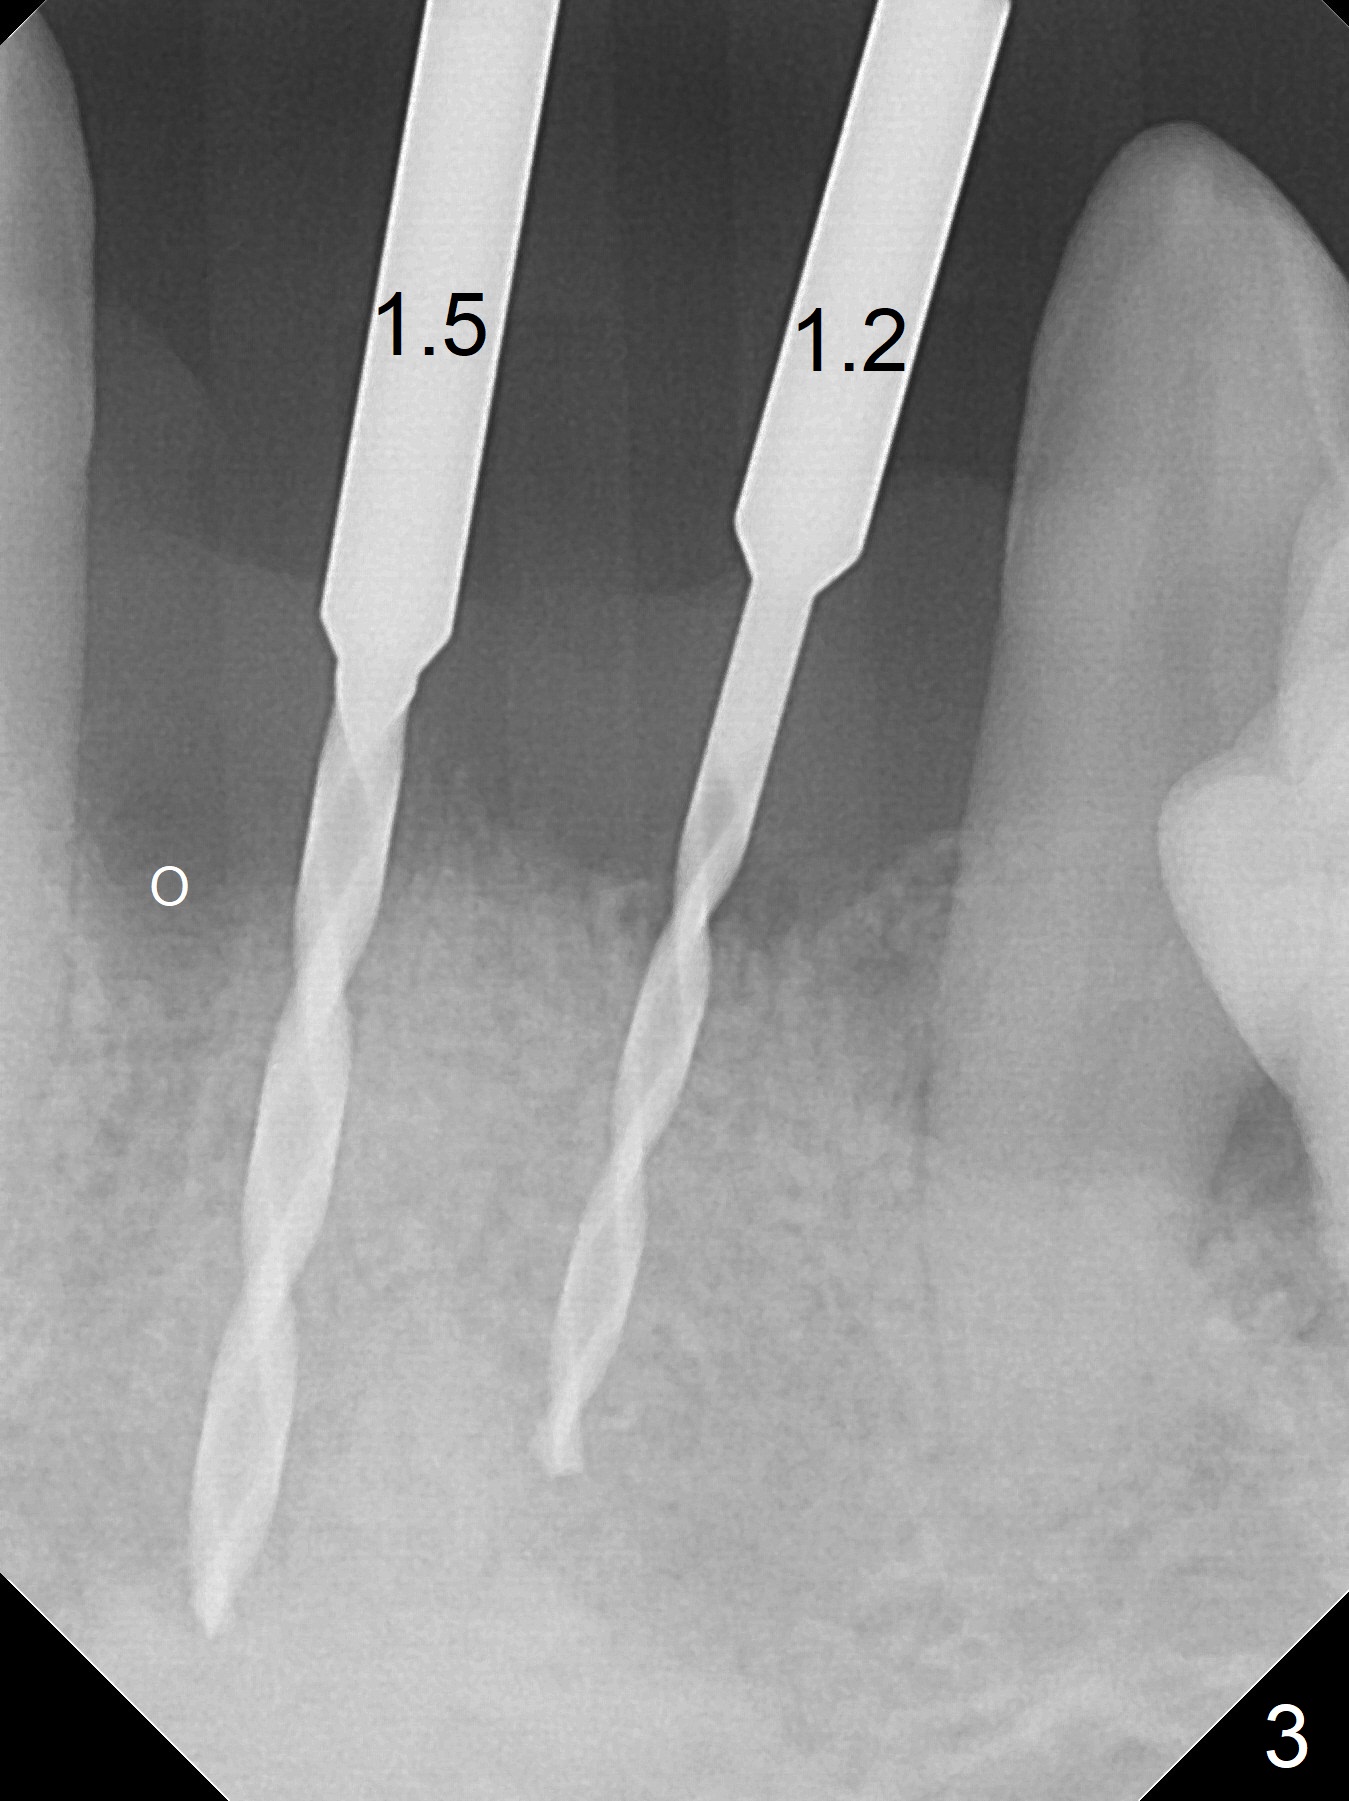

After extraction of 4 of the lower incisors, there are basically 2 sockets (#23/24 and 25/26), separated by the apparently midline bone (Fig.1 red line). In spite of using Lindamann bur to move the 25/26 osteotomy mesially, a 3x14(2) mm dummy implant remains close to the tooth #27 (Fig.2). The terminal branch of the Incisive Canal (<) is located between the lateral and central incisors. A de novo osteotomy (Fig.3 (1.5 mm drill)) is made mesial to the original one (O). While the 3x14(2) mm dummy implant is incompletely placed at #25/26, a 3x14(4) mm 1-piece one is placed at #23/24 (Fig.4). Finally the same implant is placed at #25/26 with placement of mineralized cortical/cancellous bone (Fig.5 *). When the large sockets are sutured, the supraerupted teeth #7-9 touch the lower gingiva (Fig.6). The incisal edge is reduced for clearance (Fig.7). Periodontal dressing is less likely to be dislodged with the incisal edge reduction (Fig.8,9). A provisional FPD is fabricated 1 week postop. Hard (Fig.10) and soft (Fig.11,12) tissues heal 5.5 months postop. The patient returns for crown cementation 3 months post impression (9 months postop, Fig.13,14).